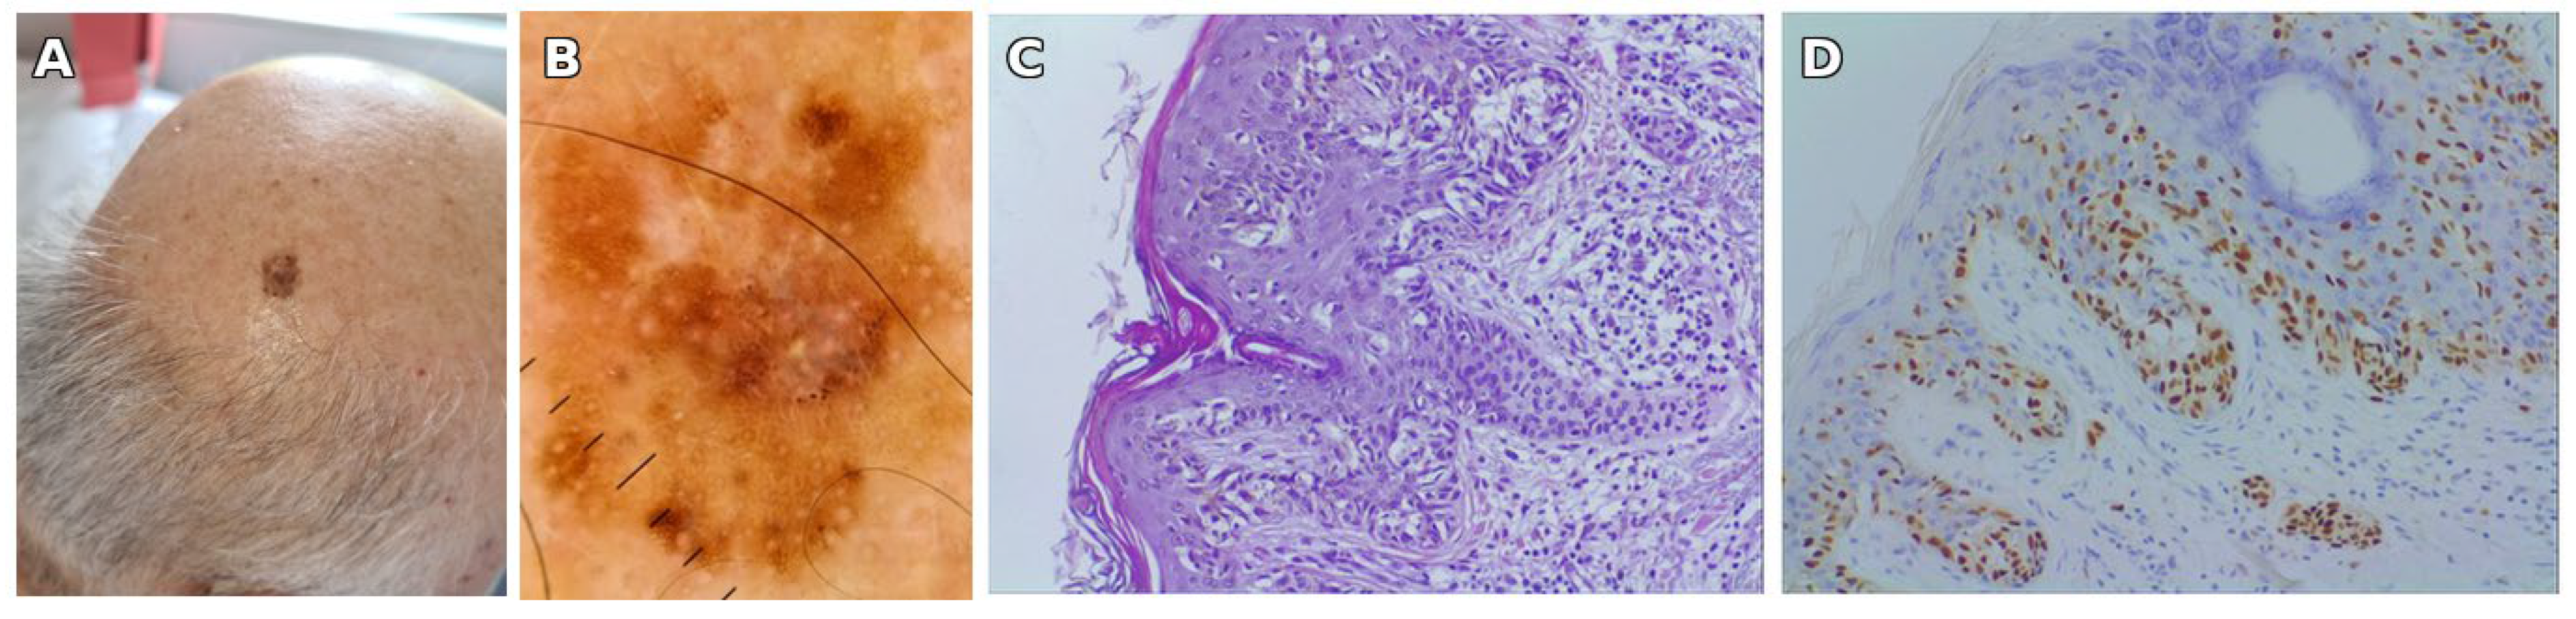

| Year (Age) | Site | Relation to SLN | Clinical Features | Histological Type | Breslow (mm) | Stage |

|---|---|---|---|---|---|---|

| 2013 (66) | Left shoulder | Within SLN | Verrucous black plaque, 10 × 8 mm, eccentric pigmentation | Superficial spreading melanoma, in situ | – | pTis |

| 2022 (75) | Left arm | Within SLN | Flat brown macule, 6 × 7 mm, atypical reticular network on dermoscopy | Superficial spreading melanoma, in situ | – | pTis |

| 2022 (75) | Posterior parietal scalp | Outside SLN | Irregular brown-black plaque, 14 × 10 mm | Superficial spreading melanoma, invasive (Clark II) | 0.3 | pT1a |